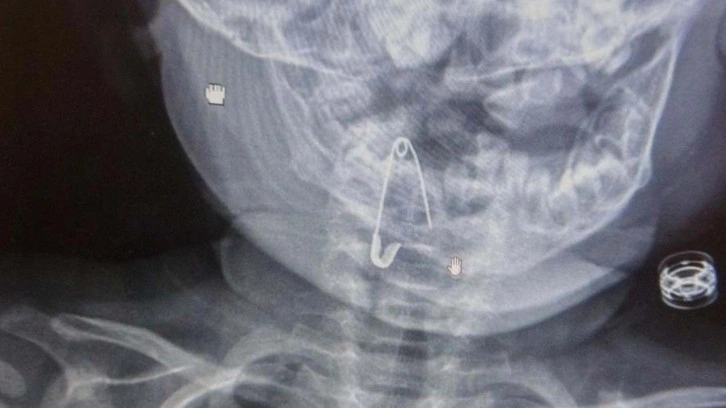

Bitlis’in Güroymak ilçesinde, Güroymak ilçesinde 8 aylık bebek, evde bulunan çengelli iğneyle oynarken onu yuttu. Öksürmeye başlayan minik çocuğun, hastanede çekilen röntgen sonucu çengelli iğneyi yuttuğu fark edildi.

Güroymak Devlet Hastanesi’nden Tatvan Devlet Hastanesi’ne ambulansla sevki gerçekleşen minik çocuk, Kulak Burun Boğaz Hastalıkları Uzmanı Operatör Dr. Hakan Tuhan tarafından yapılan başarılı operasyonla sağlığına kavuştu. Çengelli iğnenin saplı olduğu soluk borusundan çıkarılan bebek, 2 saatlik gözlemin ardından taburcu edildi.

Konuyla ilgili açıklamada bulunan Kulak Burun Boğaz Hastalıkları Uzmanı Operatör Dr. Hakan Tuhan, “8 aylık bir bebek, Bitlis’in Güroymak ilçesinden tarafımıza danışıldı. Güroymak ilçesinde çekilen röntgen sonucunda çengelli iğnenin soluk borusunun girişinde olduğunu teyit ettik. Yapılan müdahaleler sonucunda çengelli iğneyi çıkardık. Çıkardıktan sonra iki saat kadar gözlem altında tuttuk hastamızı. Daha sonrasında herhangi bir komplikasyonla karşılaşmadık ve sorunsuz bir şekilde taburcu ettik” dedi.